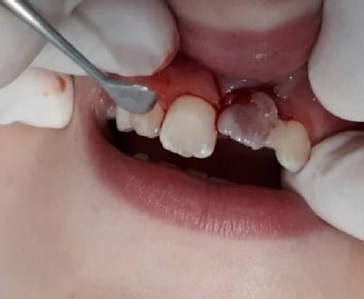

The avulsed tooth had an intact crown and a two-thirds formed root with a wide-opened apex. The dentist seized the tooth from the saline solution, holding it by the crown and not touching the root surface, and gently rinsed it with 0.12% chlorhexidine. Local anesthesia (2% lidocaine hydrochloride with 1:100000 epinephrine vasoconstrictor) was administered through labial and palatal infiltration in the affected area. The alveolar socket was gently rinsed with saline solution. The avulsed tooth was restored into the socket with slight digital pressure, ensuring its correct position. The replanted tooth was splinted with a 0.4-mm stainless steel orthodontic wire and brackets, placed on the left deciduous canine (63), the right maxillary central incisor (11), and the right deciduous canine (53) (Figure 2). The brackets were fixed away from the gingival tissues and proximal areas after etching the crown surfasse with 37% phosphoric acid for 20 seconds, rinsing with water, air drying, and applying a bonding agent and a composite resin.

The dental apex was wide open, and the crown changed color slightly. The dentist checked the occlusion and prescribed oral anti-inflammatory and antibiotic medications: ibuprofen 100 mg/mL, 20 drops twice daily, and amoxicillin 400 mg/potassium clavulanate 57 mg per 5 mL, twice daily for ten days. Homeopathic remedies were also prescribed: Symphytum CH5 associated with Marigold CH3 30 mL 5% alcohol, eight drops thrice daily for 30 days. The patient had recently received an unnecessary tetanus booster vaccine. He was advised to maintain a soft diet for 15 days and use a soft-bristled toothbrush and 0.12% chlorhexidine mouth rinse twice daily for oral hygiene maintenance.